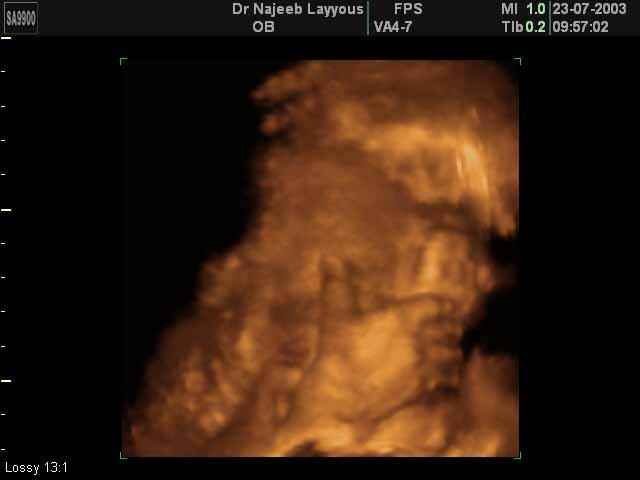

3D Ultrasound Scan Photos of Fetal Limbs | Dr N Layyous

3D Fetal Limbs Ultrasound Scan Photos